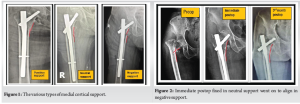

Anteromedial cortical support reduction- Radiological evaluation

In the immediate post-operative period, radiological evaluation was done based on anteromedial cortical support (AMCS). We noticed that the majority of cases (21 cases) had positive support. We also observed neutral support in 15 cases and negative support in 4 cases (Table 3 and Fig. 1).

Radiological analysis at immediate and post-operative for anteromedial cortical support

In our study, out of 21 cases of positive cortical support – 6 cases went to neutral support, those were 3 cases from Boyd and Griffin type 2, two cases from type 3 and 1 case from type 4, and other each 1cases from type 2 and type 3 went to negative cortical support from neutral cortical support and 3 cases from type 4 went to negative cortical support from neutral reduction. Finally, all the fractures united well between 3 and 5 months (Table 5 and Fig. 2 and 3).